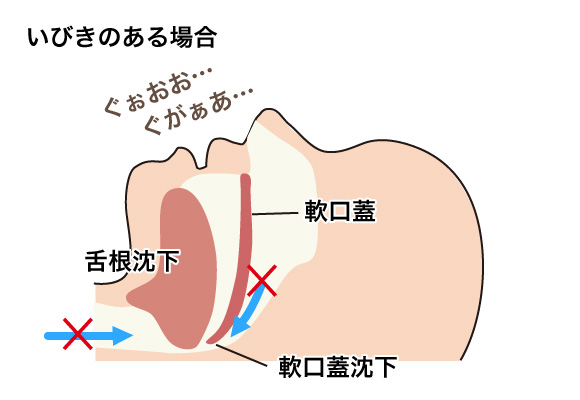

睡眠時無呼吸症マウスピース

気道が十分確保され、呼吸が妨げられません。スムーズな睡眠がとれます。

気道が確保されず、呼吸が妨げられ、十分な睡眠ができません。呼吸が止まる事さえあるかもしれません(睡眠時無呼吸症候群)